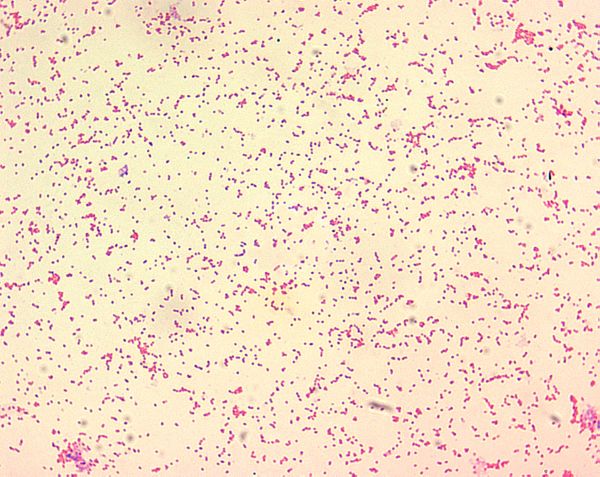

Coccobacilles à Gram -.